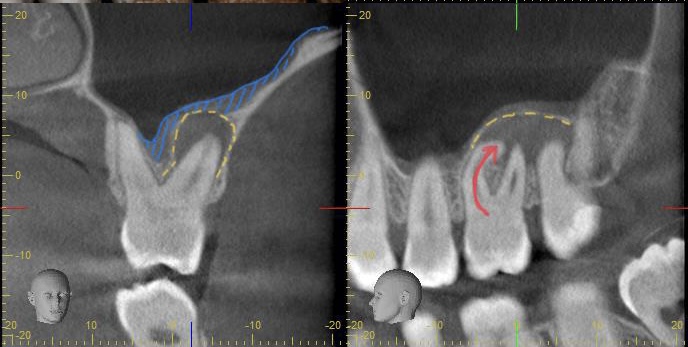

診断:CTによる精密検査で見つかった複雑な感染源

CTでしっかりと診断を行ったところ、とても深刻な状況でした。根管治療が重要ですが、それだけでは完全な治癒が望めない場合もあり、歯槽骨の再生を促す外科的処置が必要になることもあります。

こちらの患者様のように、歯槽骨のダメージが大きい症例では、根管内の感染と歯肉溝内の感染が両方の原因となっていることが多いですね。

根尖病変によりCT上で黒く写っていた部分が白っぽくなっているのがわかりますか?

溶けていた部分の歯槽骨が回復しているということです!

また、上顎洞の肥厚は収まり、頬側の歯槽骨もくっきり映っています。予想以上に歯槽骨が回復しているので、今後外科的処置をしなくても良いのではないかと判断しました。大きなダメージがあった歯なので補綴物を入れた後も欠かさずに経過観察を行い、少しでも長くご自身の歯で生活して頂きたいと思います。